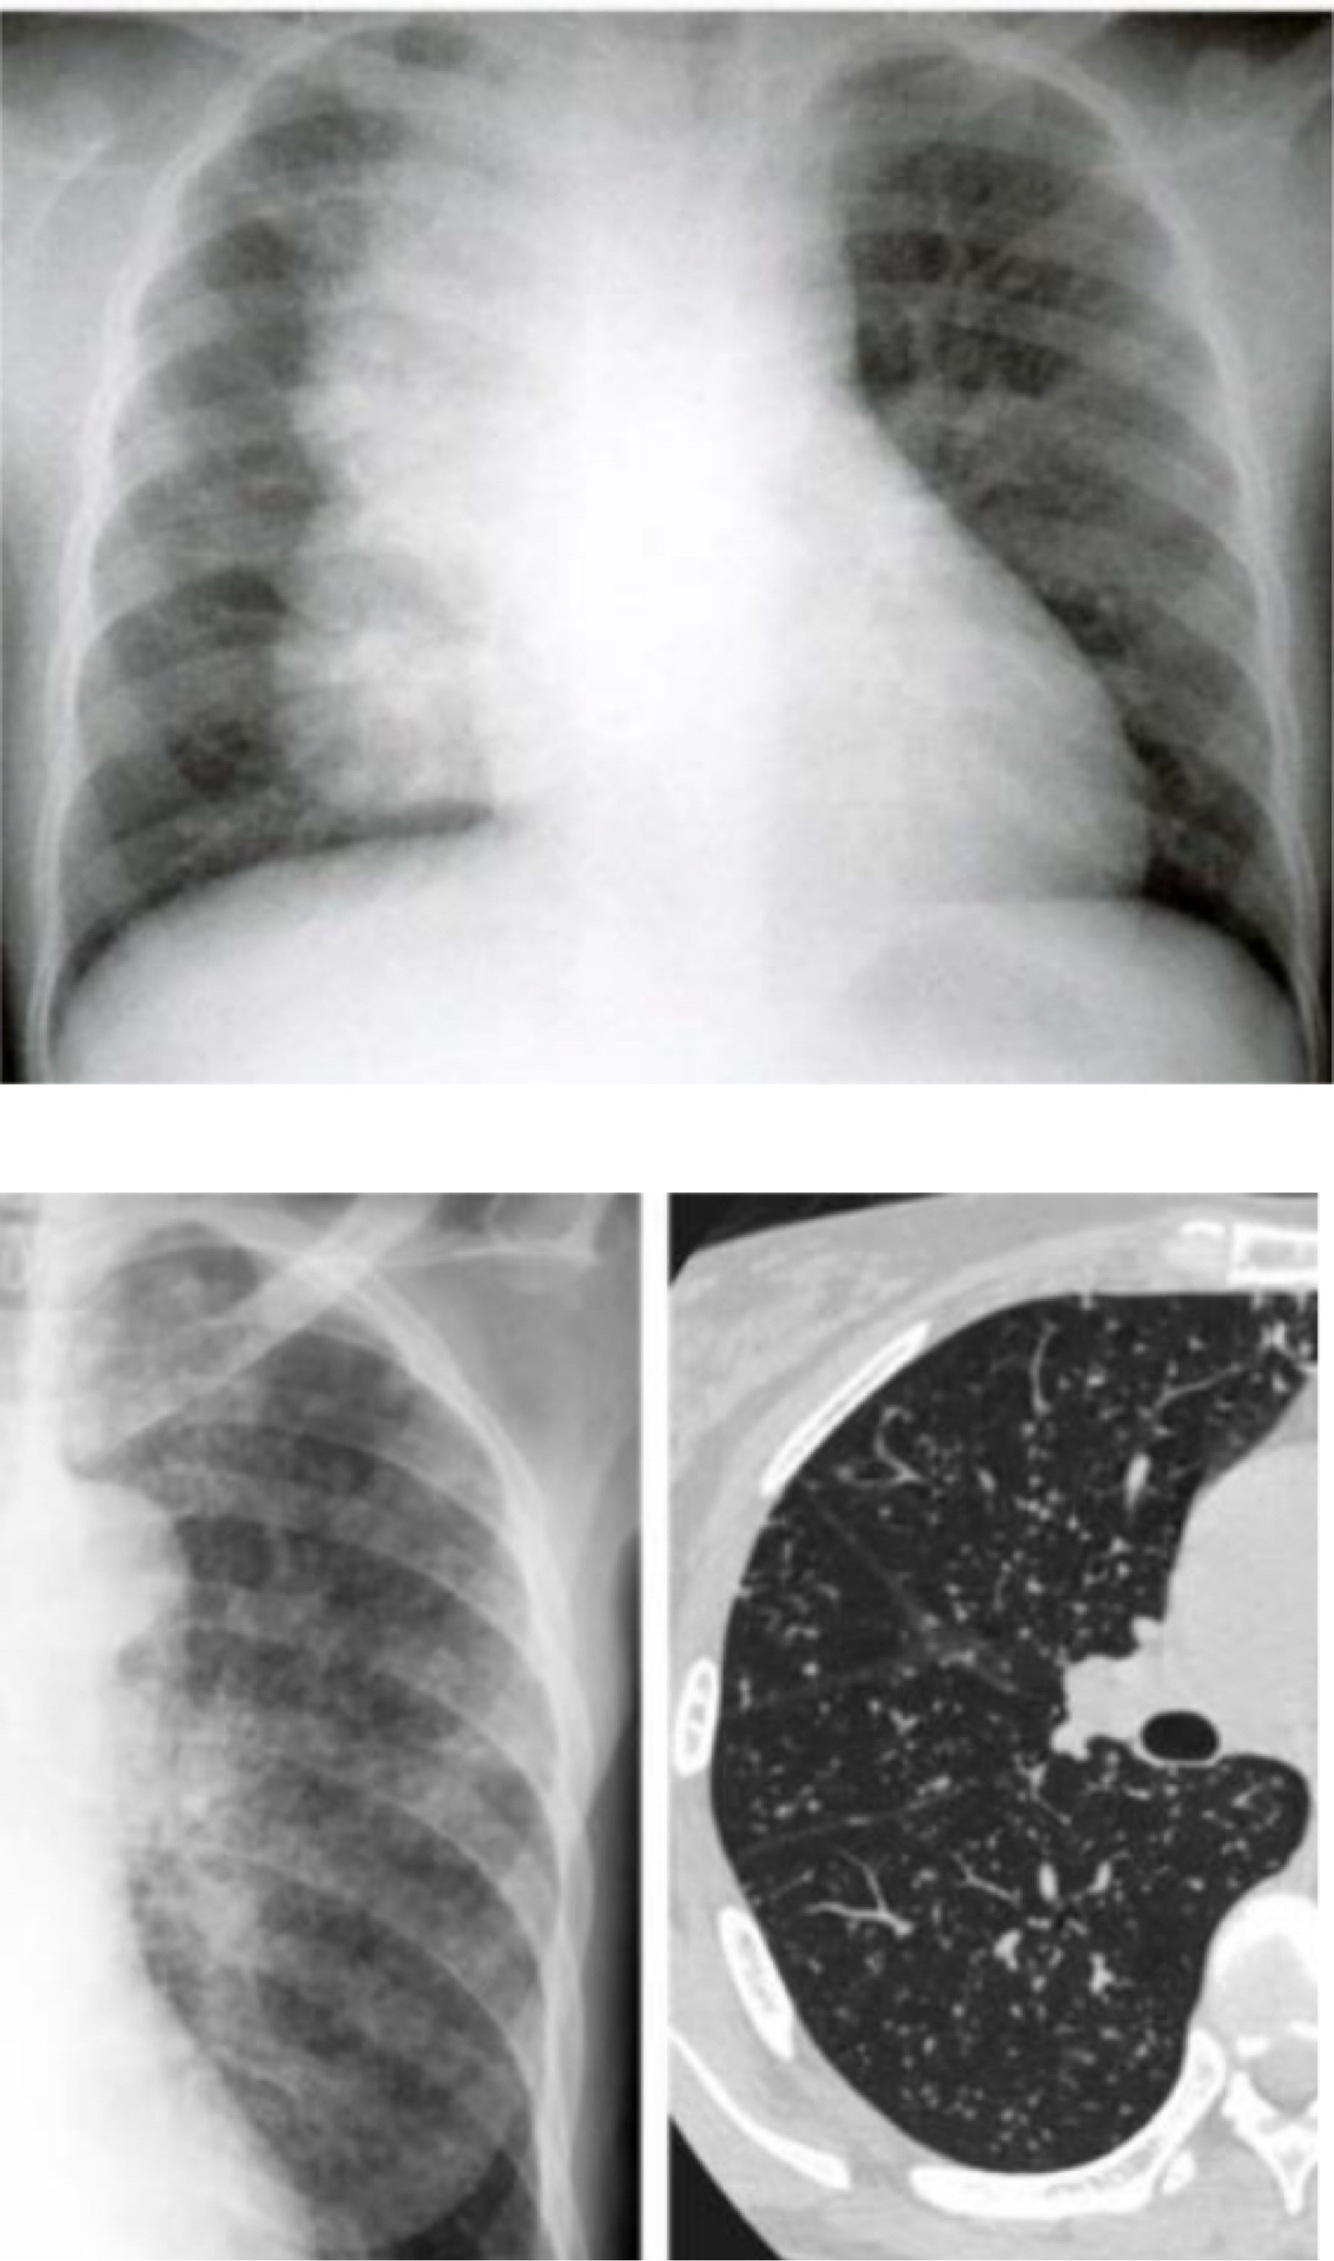

Sim, a tuberculose miliar é um tipo de tuberculose extrapulmonar. Ela ocorre quando o Mycobacterium tuberculosis se dissemina de forma descontrolada através da corrente sanguínea, afetando múltiplos órgãos fora dos pulmões. Esse tipo de tuberculose é particularmente grave e pode ser semelhante a uma "sepse" devido à sua natureza disseminada. É mais comum em indivíduos imunodeprimidos ou em crianças menores de 2 anos que não foram vacinadas com a BCG. A radiografia de tórax geralmente mostra um infiltrado micronodular difuso bilateral, que se assemelha a pequenas sementes de milho dispersas por todo o campo pulmonar, refletindo a disseminação extensa da infecção.